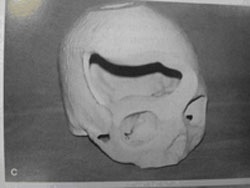

图5 头颅冠状位CT

(来自plastic and reconstructive surgery)

图7 三维重建CT

(图片来自于病案收藏)